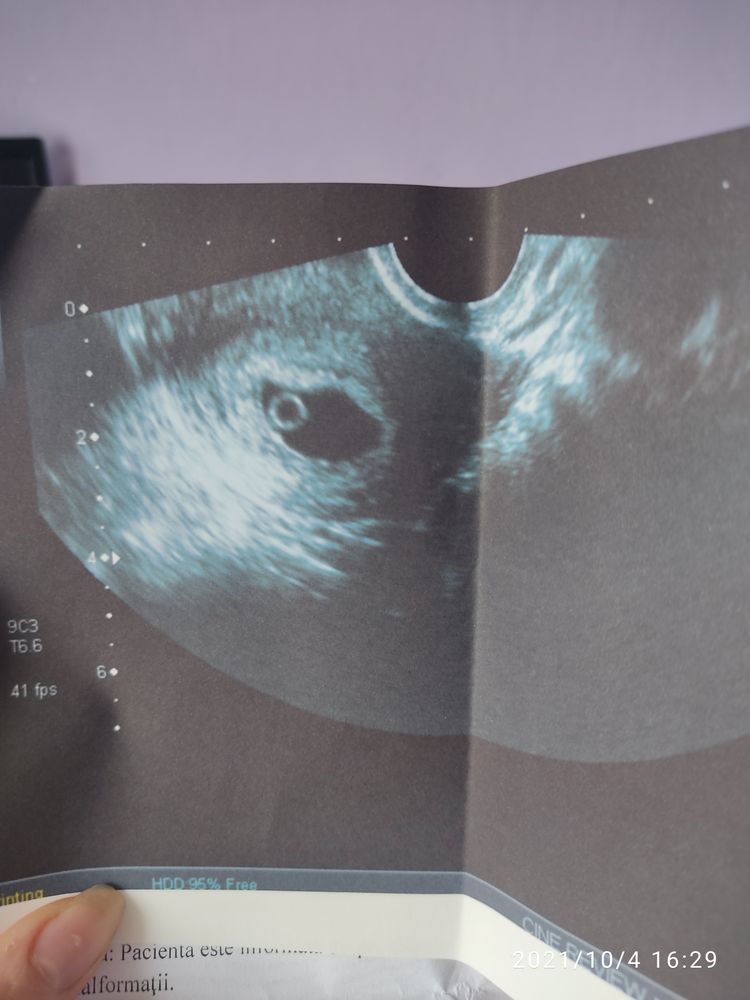

У меня 5 недель и не увидели на УЗИ эмбрион,у кого так было.

На 21дпп, увидели плодное тело. В УЗИ не написали ни слова про эмбрион, но сказали через неделю прийти и может будем сб смотреть.

Надо было недель в 6-7 акушерских идти там и эмбрион был бы и сб уже возможно бы нашли, так у вас только жм видно))